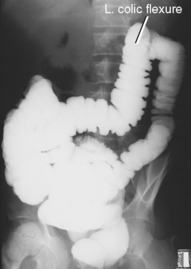

Both right and left lateral decubitus are commonly taken as part of a double-contrast series.

R and L lateral decubitus (double contrast)